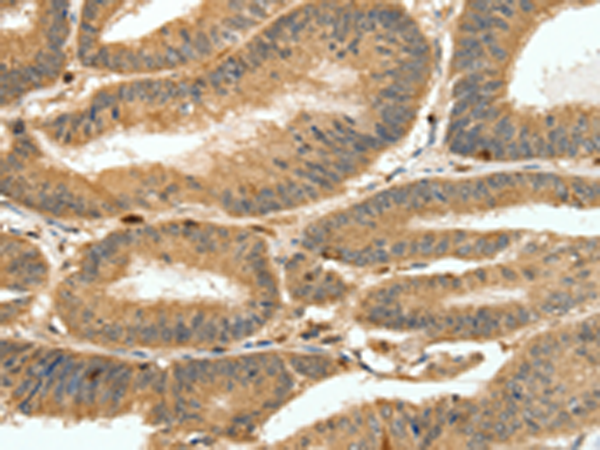

分类: 科研抗体货号: P04383别名: NGX6, NAG-5, C9orf127, RP11-112J3.10应用: IHC反应种属: Human, Mouse